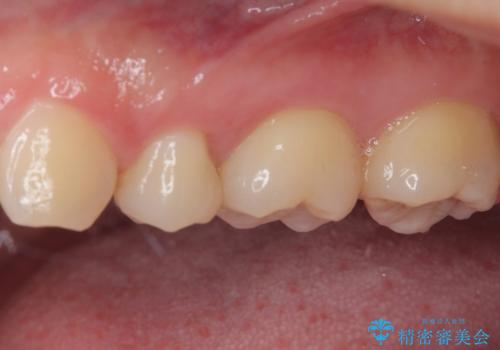

奥歯に物が挟まる セラミックインレーでのむし歯治療

- 食事の度に物が挟まるとのことで来院された患者様です。

目視でも欠損が認められ、レントゲン写真からもむし歯が認められる状態でした。

患者様と相談の上、セラミックインレーで精密な修復治療を行うこととしました。

精密な型取りと、ラバーダム防湿下での接着操作により、歯と詰め物の隙間を最小限にとどめることができ、良好な長期予後が期待できます。